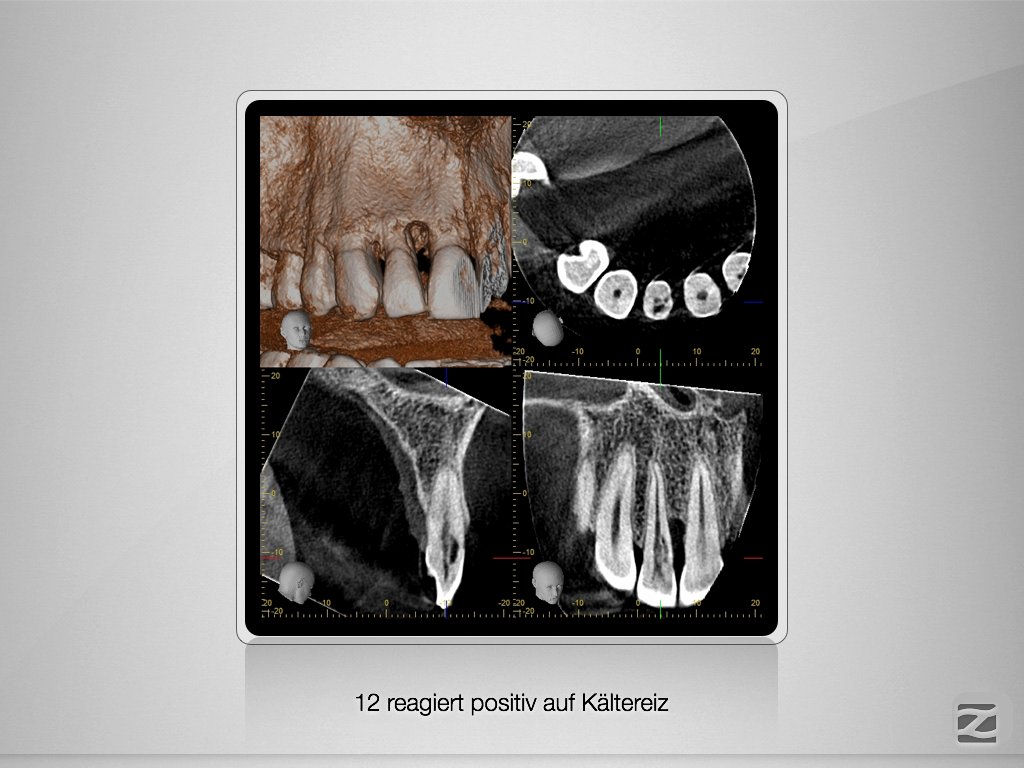

Externe Resorption mit Perforationen